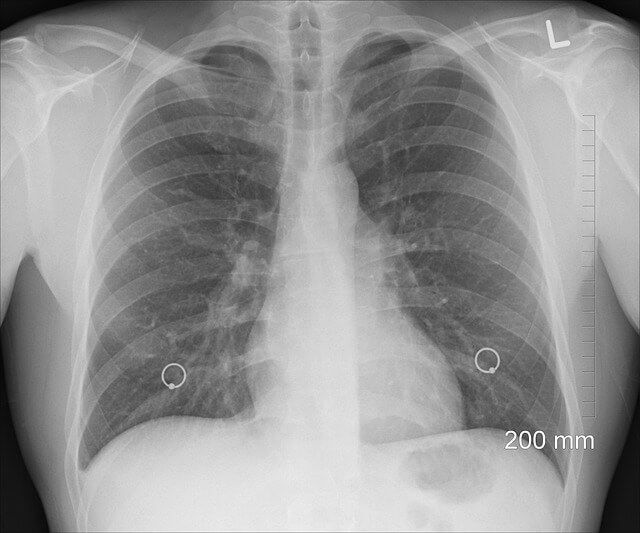

폐에 물이 차는 원인

폐부종 또는 흉수가 발생하는 원인은 다양하며, 그에 따라 치료법도 다릅니다.

심부전

심장이 제대로 기능하지 못하면 폐에 체액이 축적될 수 있습니다.

폐렴 및 감염

세균이나 바이러스 감염으로 인해 폐 내 염증이 발생하면서 물이 차는 경우가 많습니다.

신장질환

신장이 제 역할을 하지 못하면 체내 수분이 조절되지 않아 폐에 물이 찰 수 있습니다.

폐암 및 악성 질환

폐암, 전이성 암이 폐에 퍼지면서 흉수가 발생할 수 있습니다.